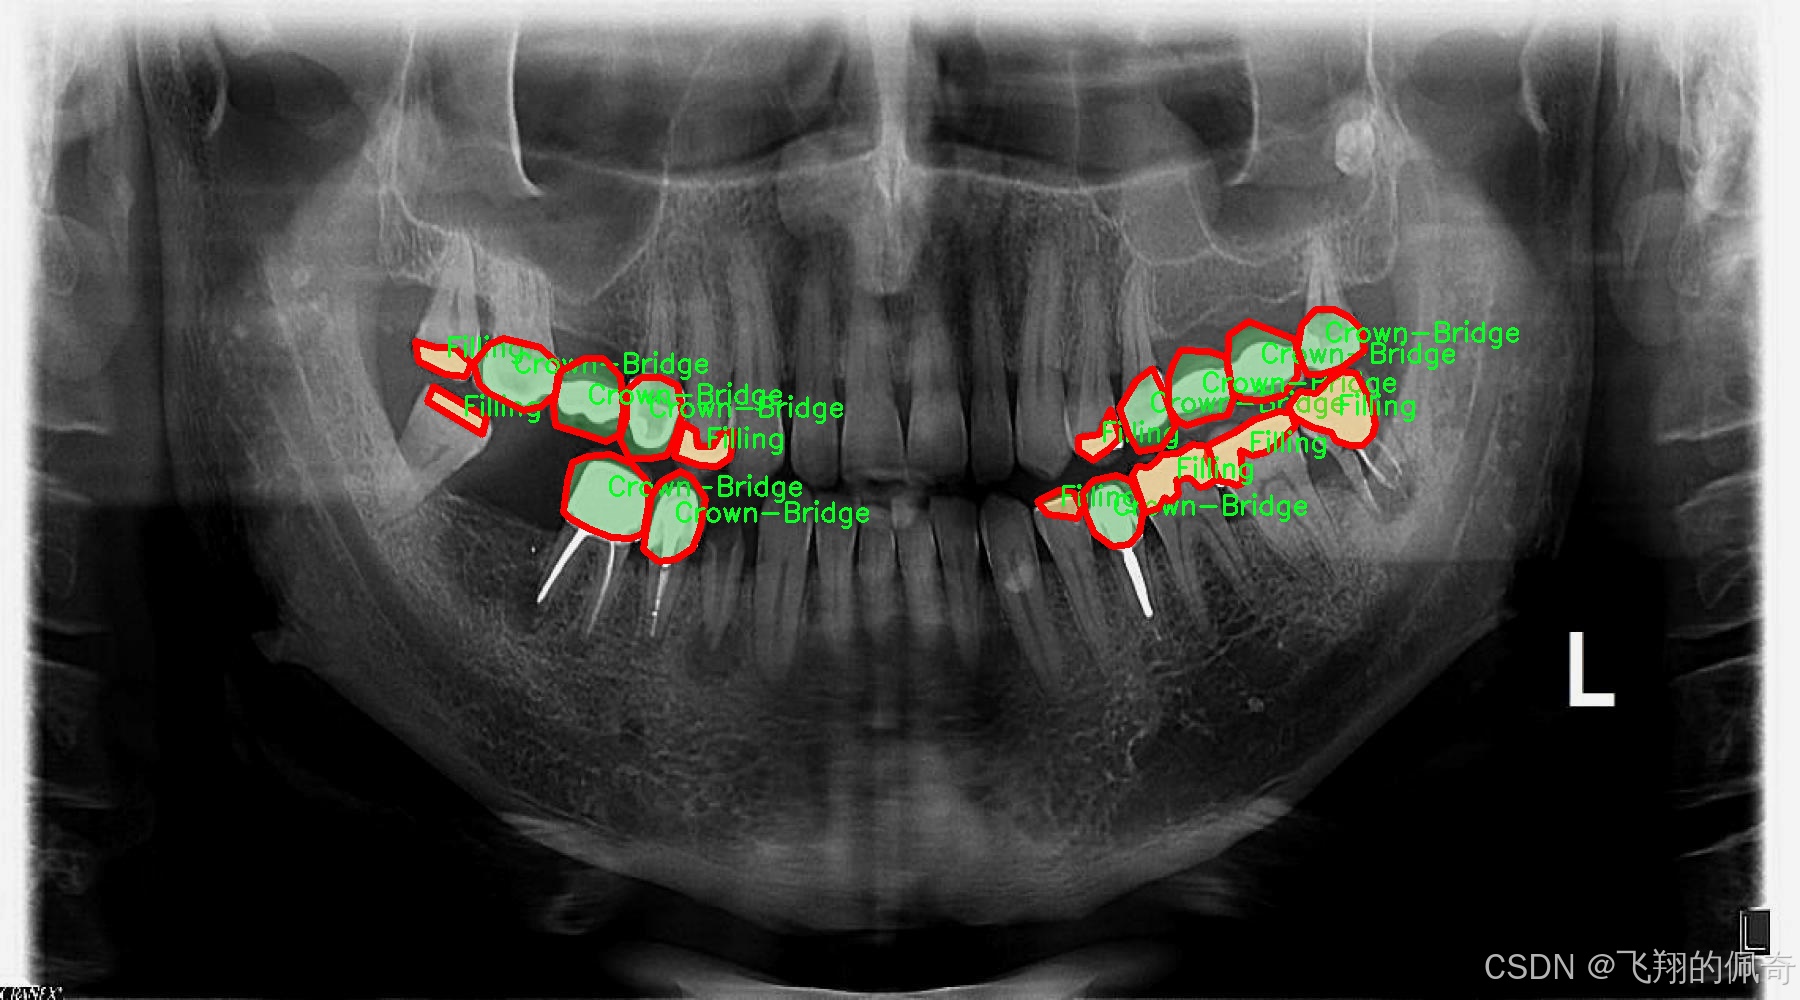

图片效果

在现代牙科医学中,龋齿的早期诊断与治疗至关重要,而图像分割技术在这一领域的应用为牙科医生提供了更为精确的工具。为此,我们构建了一个名为“tooth segmentation”的数据集,旨在训练改进版的YOLOv8-seg模型,以实现对牙齿病变图像的高效分割。该数据集专注于八种不同的牙齿病变类型,涵盖了从龋齿到各种修复体的多样性,确保模型能够识别和分割这些关键特征。

“tooth segmentation”数据集包含八个类别,分别为:龋齿(Caries)、牙冠与桥(Crown-Bridge)、填充物(Filling)、植牙(Implant)、后螺钉(Post-screw)、根管填充(Root canal Obturation)、牙冠(crown)以及再植体(implant)。这些类别不仅代表了牙齿的不同病变状态,还涵盖了牙科治疗中常见的修复和重建过程。这种多样性使得数据集在训练过程中能够有效地提高模型的泛化能力,帮助其在实际应用中更好地适应不同的病例。